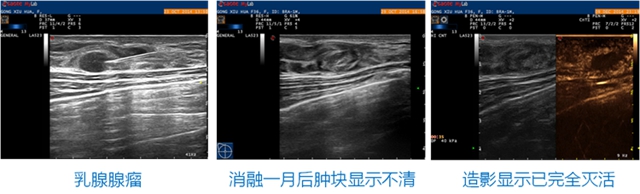

乳腺结节激光消融 已有不少国内外杂志文献和临床实践明确了激光消融对于乳腺肿瘤有极佳的临床疗效;对于<1.5cm的恶性肿瘤,均获得彻底消融,而对于1.5—2cm以及>2cm的恶性肿瘤,完全消融率为88%和67%,对于较大的乳腺恶性肿瘤,宜采用多针联合消融为佳。而对于乳腺良性肿瘤的激光消融,同样已经受到学者关注获得了良好的临床效果。